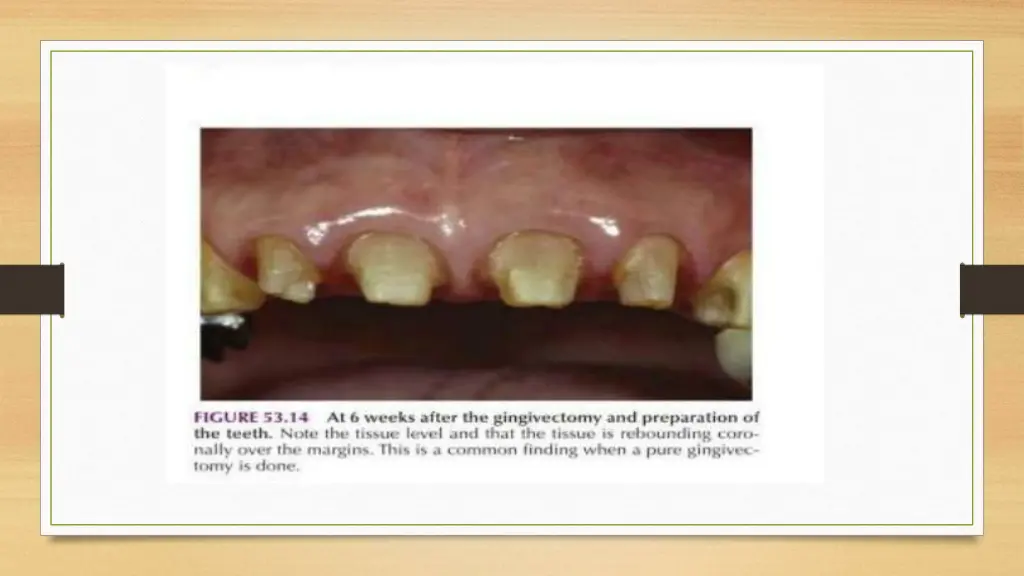

MARGIN PLACEMENT GUIDELINES i. If the sulcus probes 1.5mm or less,Place the margin 0.5mm below the gingival crest. ii. If sulcus probes more than 1.5mm- Place the margin 1\2 depth of the sulcus below the crest. iii. If sulcus probes more than 2.0mm, Esp. On facial aspect- Gingivectomy should be done & create a 1.5mm sulcus Apply Rule No. 1

Anterior Aesthetic Surgery More Imp. In Anterior Region Gingivectomy, Apically displaced flaps with osseous recontouring & Use of Orthodontics in positioning the gingiva apically or coronally by Extruding or Intruding the teeth. Computer Imaging for Visual preview A Stone cast of patient s own teeth may be used Composite or Acrylic veneer is constructed on the cast extending gingivally in a correct position.